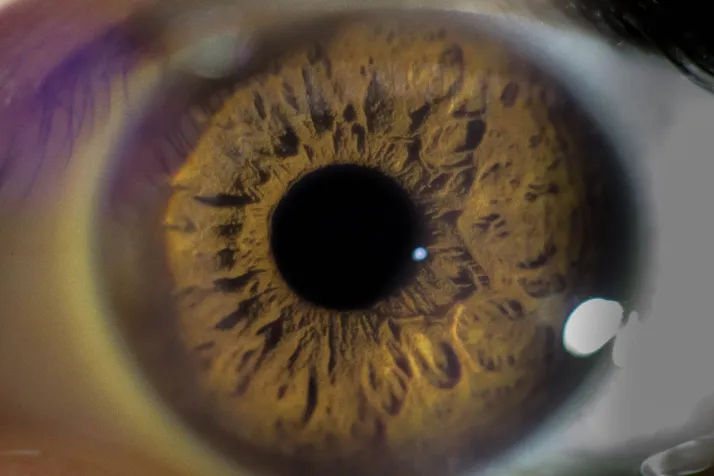

La nueva normalidad viene acompañada de un repunte estimado en un 15% de las patologías oculares. La principal causa es el aumento de la exposición a dispositivos electrónicos y pantallas en los tres últimos meses. Las dolencias asociadas a la disminución del parpadeo por fijar la vista en la pantalla -de 12 o 14 veces por minuto a una o dos- y la evaporación de la película de lágrima natural del ojo son el síndrome visual del ordenador y el ojo seco. A estas se les suman el incremento de conjuntivitis y el aumento de las miopías.

Sin embargo, las condiciones de teletrabajo y ocio a través de los dispositivos no son las únicas causas del aumento de las enfermedades oculares. La doctora Marta Mármol, oftalmóloga del Centro de Oftalmología Barraquer, apunta a que el estrés negativo sufrido durante estos meses es también la razón de nuevos cuadros clínicos.

Según el grado de estrés sufrido, de su duración en el tiempo y de las características de cada individuo, las manifestaciones a nivel ocular varían.

Las más frecuentes e importantes son: mioquimias, temblores o espasmos localizados alrededor de los párpados "tics"; blefaritis, inflamación de los párpados; coroidopatía central serosa, afectación de la mácula, que es la zona más importante de la retina; o incluso en los casos más severos puede llegar a la pérdida de visión.